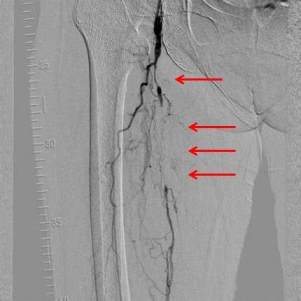

閉塞性動脈硬化症の治療は?

動脈硬化の原因となる、喫煙、高血圧、糖尿病、高脂血症などの治療を行います。症状が改善しない場合は、血管内の血液の流れを良くする薬を内服する薬物療法を行います。それでも症状の改善が見込めない時は、病変のある血管の部位や範囲を考慮して、血管内治療(血管拡張術)もしくは手術(バイパス手術)を行います。血管内治療の入院期間は2泊3日

(1泊2日も可能)です。体を動かしたり、歩いたりすること(運動療法)も非常に重要な治療の一つです。

治療法の選択にあたっては、患者さんの症状や状態などを考慮して決めますが、組み合わせて行うこともあります。

血管内治療前

血管内治療後